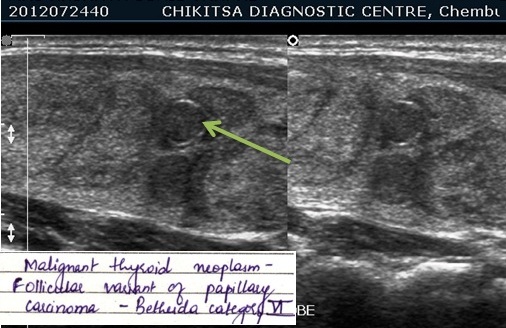

An ultrasound examination of the thyroid is typically used to determine if the thyroid disease is diffuse or noduar and to analyze the appearance of thyroid nodules.